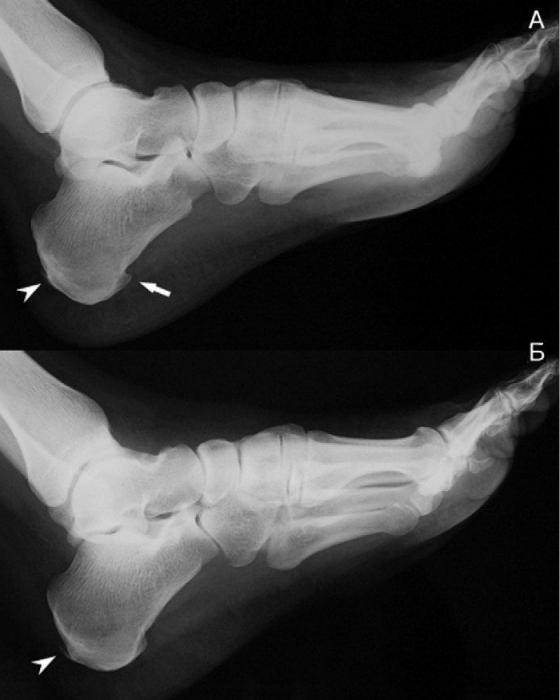

Бессимптомное протекание заболевания